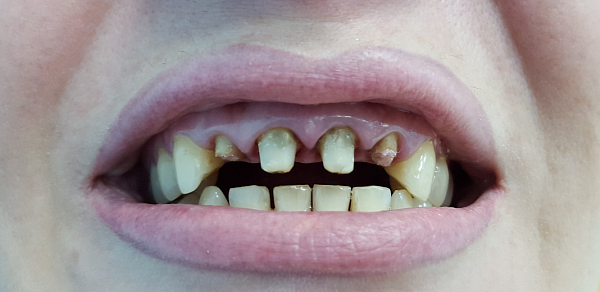

Установка акрилового протеза

Пациент в возрасте 50 лет имел обширные проблемы с зубами, что привело к их полной потере, за исключением одного. Чтобы восстановить необходимую функциональность и эстетику улыбки, была проведена процедура установки коронки из высококачественного диоксида циркония для спасения последнего оставшегося зуба. В дальнейшем для пациента были изготовлены и успешно установлены съемные акриловые протезы как для верхней, так и для нижней челюсти.